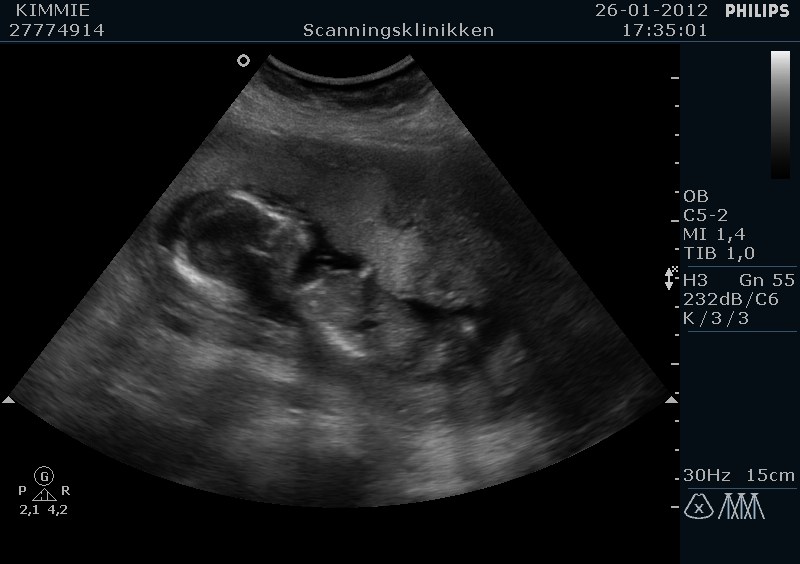

Jeg havde en tyk moderkage som lå ud mod maven og derfor var babs godt gemt, så det tog lidt ekstra tid for at 100 % at kunne identificere kønnet.

Men den er god nok, vi venter en lille....... PIGE mere...

Til sidst lige et par billeder

Vedhæftede fotos (klik for at se i fuld størrelse)